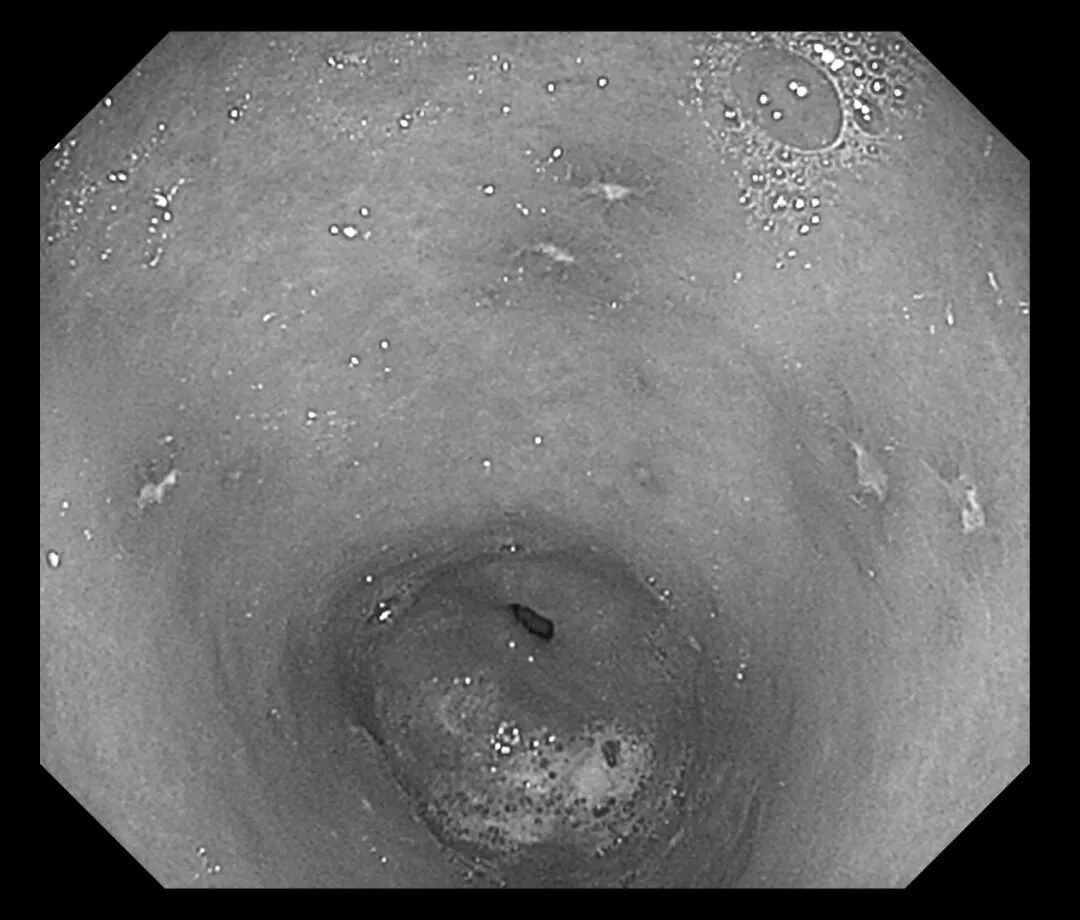

接诊医生刘润萍详细询问病史后,敏锐地意识到这可能是一例典型的“药物性胃溃疡”病例。为明确诊断,在评估患者情况后为其安排胃镜检查。检查结果令人大为震惊:胃窦、胃体等多处黏膜可见十余个直径0.3-0.5cm不等的溃疡灶,部分表面覆有白苔,周围黏膜充血水肿明显。结合患者近期用药史,考虑为“非甾体抗炎药相关性胃溃疡”。

(胃窦溃疡)